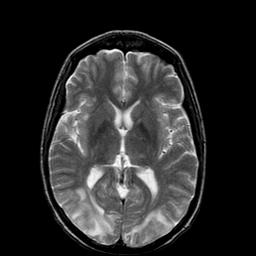

Hypertensive Encephalopathy: MRI/SPECT overlay -- Slice #10

[Home][Help][Clinical] Slice 10